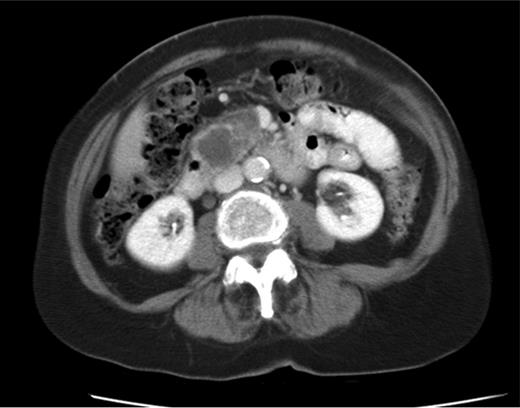

CT shows cystic mass in the uncinate process of pancreas measuring 4 cm in 2008.